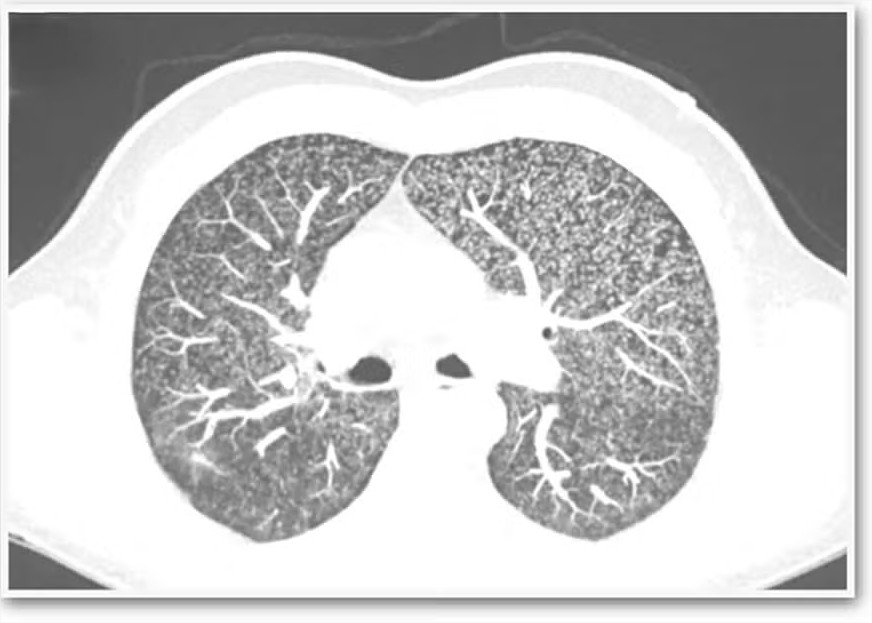

Após análise do conjunto de sintomas, o paciente passou por tomografias do tórax, abdômen e pelve. As imagens revelaram nódulos disseminados nos pulmões, compatíveis com tuberculose miliar, forma grave da doença em que a bactéria Mycobacterium tuberculosis (ou, alternativamente, Mycobacterium bovis, ligada a bovinos e cervos) se espalha pelo organismo, formando pequenas lesões.